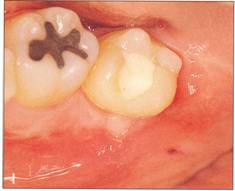

Fi 545e45f g 5-8cc After transplantation. Fi 545e45f g 5-8dd One week after transplantation. |

|

Fi 545e45f g 5-8ee Six weeks after transplantation. Fi 545e45f g 5-8ff Clinical view 6 weeks after trans plantation |

Fi 545e45f g 5-8gg Three months after transplantation. Inflammatory root resorption is ob. served on the distal aspect of the donor tooth. Root canal therapy was started immediately. Fi 545e45f g 5-8hh One month after temporary obturation with calcium hydroxide. Arrest of root resorption was confirmed and orthodontic treatment was started. |